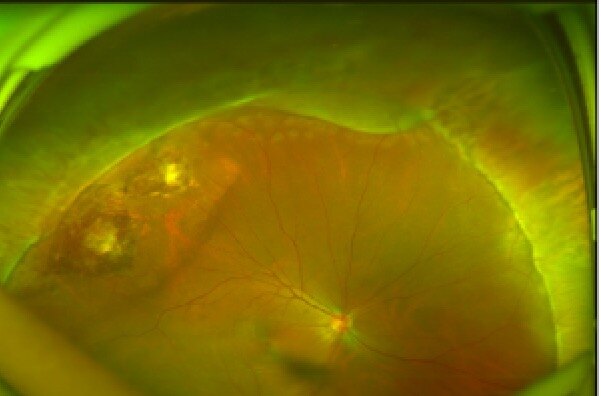

糖尿病性視網(wǎng)膜病

治療前患者左眼視物不見數(shù)月,未重視,左眼增殖性糖尿病性視網(wǎng)膜病變、牽拉性視網(wǎng)膜脫離治療后治療后50天(患者外地回來復(fù)診)玻璃體切割手術(shù)后,左眼視網(wǎng)膜形態(tài)可,黃斑區(qū)網(wǎng)膜水腫,血管走行尚可,目前矯正視力0.1,需門診進(jìn)一步補(bǔ)充些視網(wǎng)膜光凝